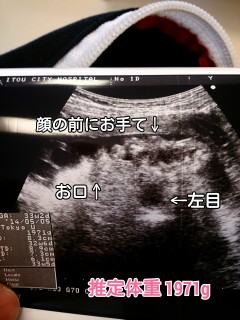

顔に手が被って最近は中々うまく撮れません(>_<) ベビーの推定体重は1971g、1週間くらい大きいかな。 心臓のお部屋も4つしっかりあって、人間ってすごいなーと。 毎日しゃっくりもしてます(笑)!